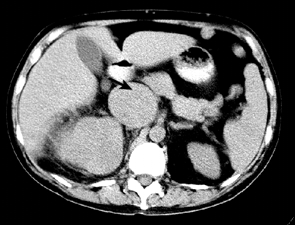

Увеличение размеров, дефекты заполнения почечной вены указывают на ее вовлечение в опухолевый процесс. Одновременное контрастное усиление опухоли и крови в НПВ ограничивает использование РКТ для выявления венозной инвазии. Общая точность РКТ в диагностике опухолевого тромбоза составляет от 68 до 95% (рис. 9).

Рисунок 9. КТ больного раком правой почки с опухолевым тромбозом НПВ. Стрелка указывает на резко расширенную НПВ